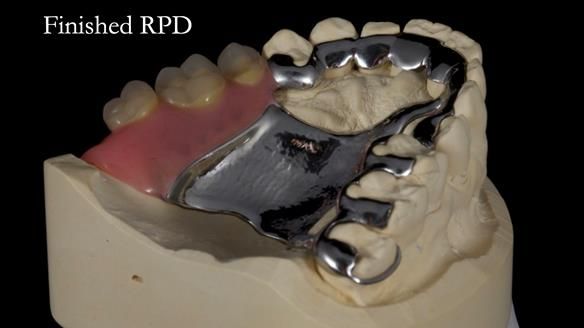

Welcome to Newsletter 64. I'll walk you through the process of providing a Mk 2 metal-based partial denture (RPD), for Ian a retired Veterinary Surgeon aged 78. The RPD was made at an increased vertical dimension and acted as an occlusal stabilisation splint - reducing the wear and bite force on the remaining natural teeth.